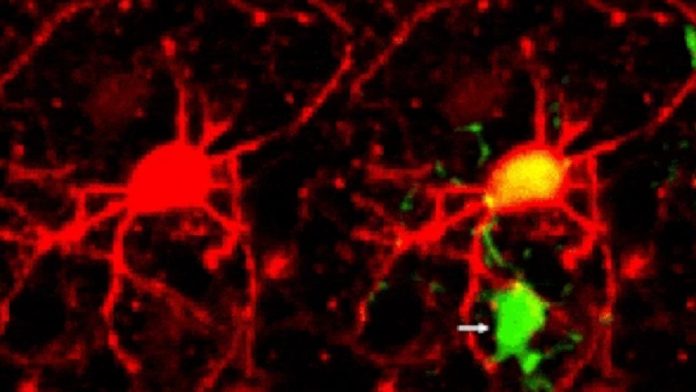

ცნობილია, რომ ჩვენს თავის ტვინს აქვს ნარჩენების მოსუფთავების ვრცელი სისტემა, რომელიც ბიოლოგიურ გზებს მკვდარი და ტოქსიკური ნეირონებისგან წმენდს. ახლახან, პირველად ისტორიაში, ლაბორატორიაში თაგვებზე ცდისას მეცნიერებმა ამ პროცესს ვიდეო გადაუღეს.

ჯერ კიდევ ბევრი რამ არ ვიცით იმის შესახებ, როგორ წმენდს ტვინი საკუთარ თავს მკვდარი ნეირონებისგან, როგორ რეაგირებს მათთან; შესაბამისად, ახალი კვლევა შეიძლება, წინგადადგმული დიდი ნაბიჯი იყოს ამ მიმართულებით, მიუხედავად იმისა, რომ ჯერ ისიც არ არის დადასტურებული, ასეთივე გზით მოქმედებს თუ არა ადამიანის თავის ტვინიც.

„პირველი შემთხვევაა, როდესაც ცოცხალი ძუძუმწოვრის ტვინში ეს პროცესი ვიხილეთ“, — ამბობს იელის უნივერსიტეტის მედიცინის სკოლის ნევროლოგი ხაიმე გრუცენდლერი.

გარდა ამისა, აღმოჩენამ შეიძლება გაგვიადვილოს ასაკთან დაკავშირებული ნევროლოგიური აშლილობების სამკურნალო საშუალებათა შექმნაც; ამისათვის კი მეცნიერებმა უფრო მეტი უნდა იცოდნენ როგორ მოქმედებს ტვინის გასუფთავების სისტემა.